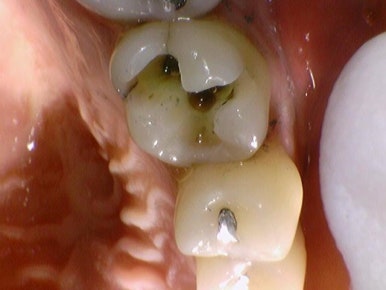

오늘은 오래된 아말감 주변으로 2차충치가 생겨서

또는 아말감이 파절되어서 떨어져 나가서,

아말감 색이 보기 싫어서 등등의 이유로

아말감을 뜯어내고 다른 치료를 한 사례를 알아보고자 합니다.

아말감을 세라믹인레이로 교체 (1.아말감상태 2.아말감제거시 충치 3.세라믹인레이 장착)